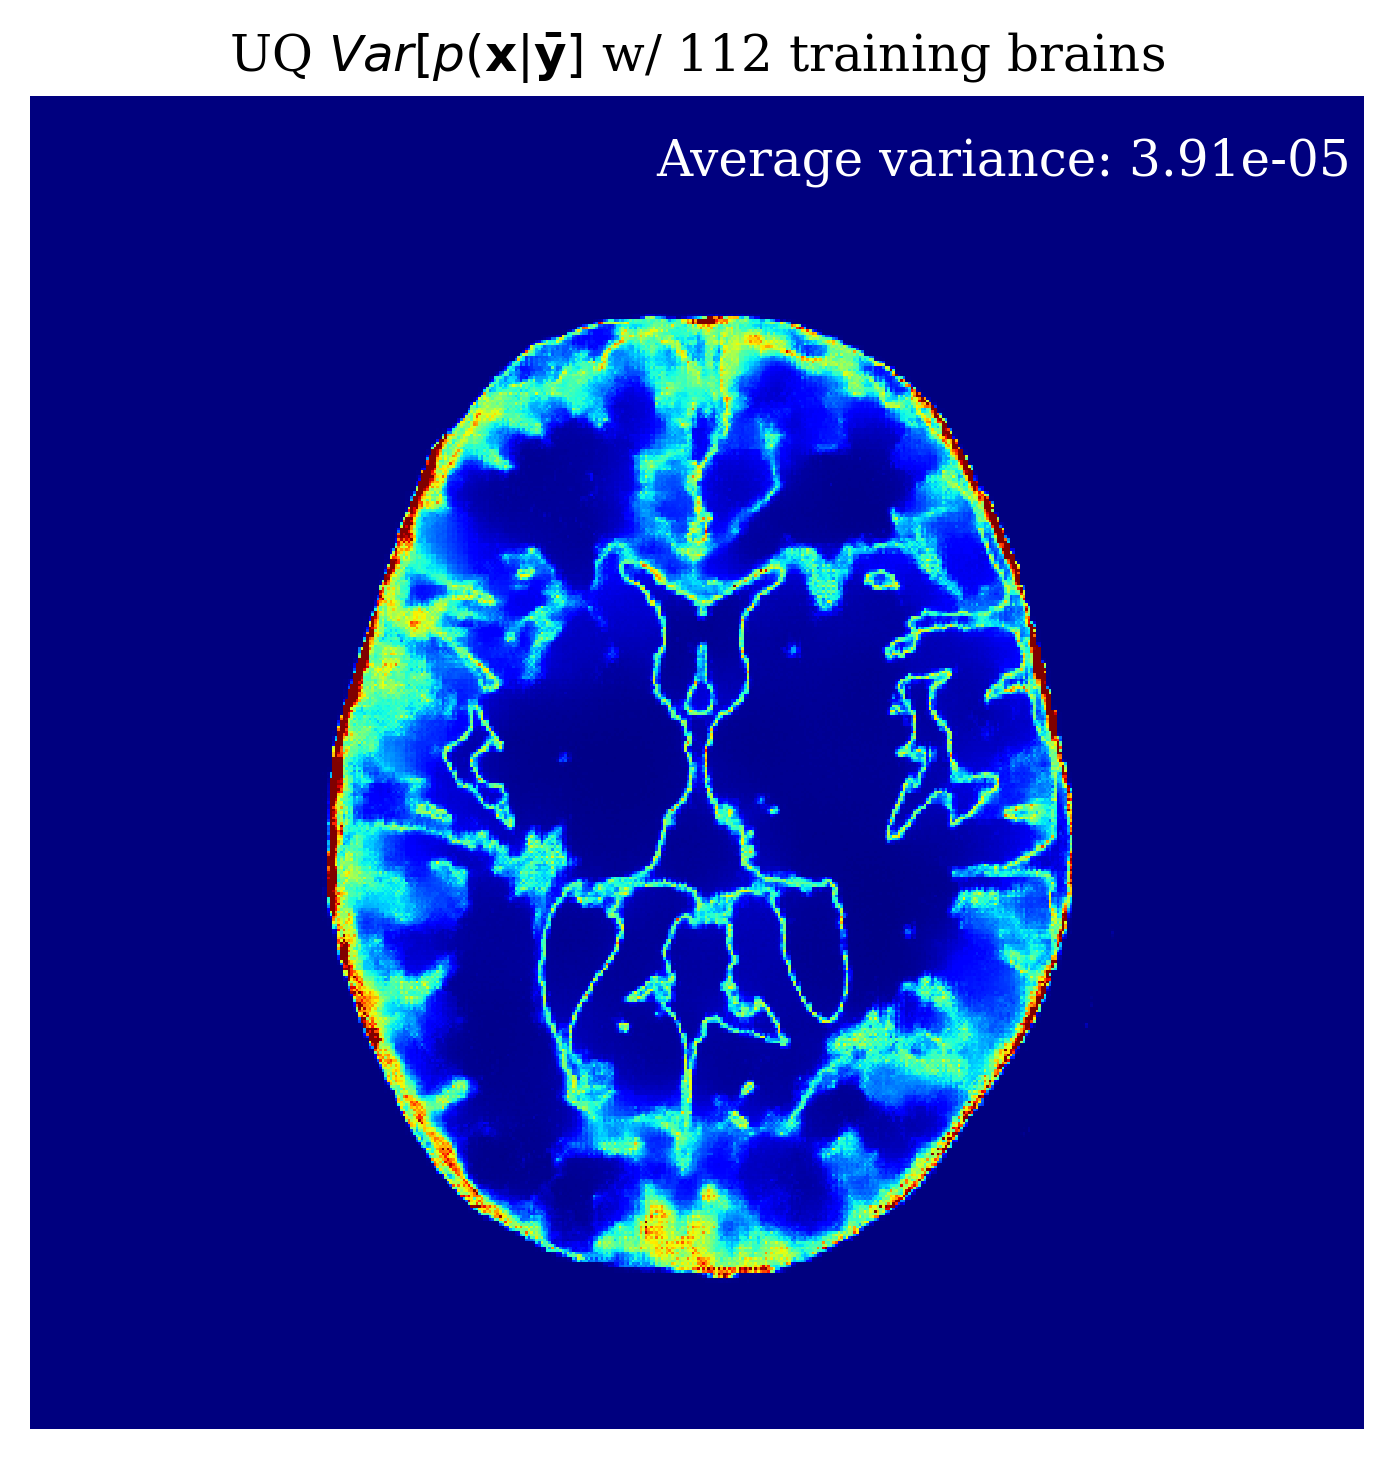

Since our method is Bayesian, its UQ results depend on how well it has learned the prior from training examples. In the case of conditional normalizing flows the prior is not explicitly accessible from the network since the network directly learns to sample the conditional distribution. Nonetheless, we would like to gain intuition on the effect of more training samples on the methods performance. In \figurereffig:trainingsize, we demonstrate the effect of increasing the training dataset size, on the posterior mean quality and on the UQ map that is produced. We observe from \figurereffig:trainingsize that as training samples increase, the posterior mean gets closer to the ground truth and that the UQ map becomes more contracted. These observations are similar to what happens when we increase the amount of observed data as explained in \sectionrefsec:uncertainty.

\subfigure

\subfigureUQ

\subfigureError

|

\subfigureGround truth